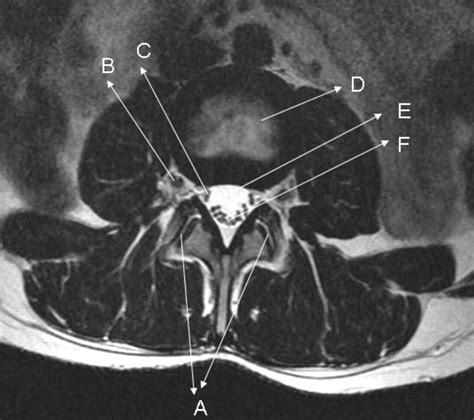

The cervical spine comprises the top seven vertebrae of your spinal column, labeled C1 through C7. This area is highly complex and functionally vital, as it protects the spinal cord and allows for a wide range of head and neck movement. An MRI of the cervical spine provides a comprehensive view of several critical components:

• Intervertebral Discs: The soft, cushion-like structures between the vertebrae.

• Spinal Cord and Nerves: The neural pathway that transmits signals throughout the body.

• Soft Tissues: Including ligaments, tendons, and muscles that support the neck.

• Bone Marrow and Vertebrae: To check for tumors, infections, or fractures.